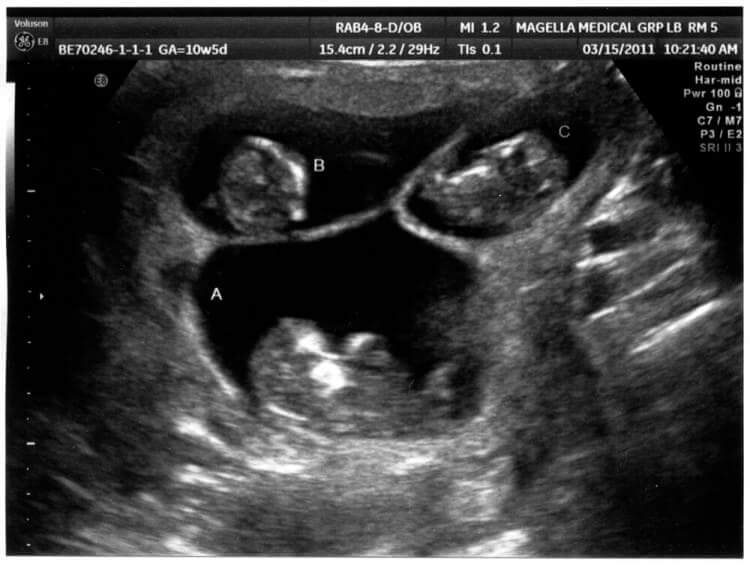

Sarah and Andy couldn't believe what they heard and they took some time to absorb the thrilling news. As they were involved with previous mothers, they were also there for the third mother at every step. They got super excited when the third mother invited them to an ultrasound appointment.

At the appointment, the couple saw their new child for the very first time. However, the scan showed something else that surprised everyone. The birth mom was actually carrying three babies instead of one.

Not One, Two, But Three Babies

The birth mother, doctor, Sarah, and Andy were completely shocked when they saw there were three heartbeats on the ultrasound monitor. They didn't lose hope when the first mother decided to keep the baby, they remained resilient when the second mother also decided to keep her baby and they were expecting just one bundle of joy. But they didn't know that the universe was planning on making up for previous chances that didn't deliver the results the couple wanted.